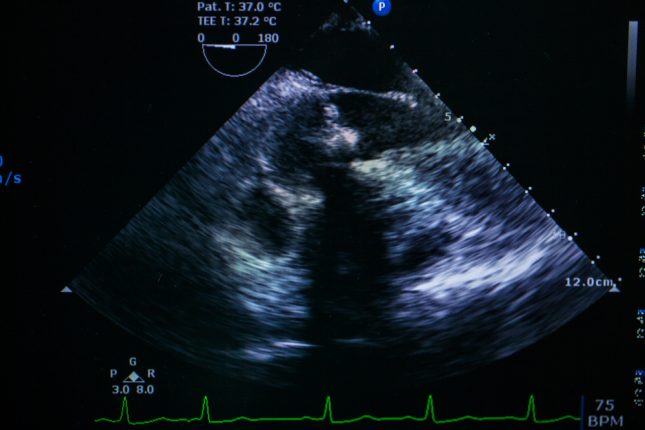

בקבלתה בוצעה אקוקרדיוגרפיה חוזרת שחשפה את העיבוי של המחיצה הבין-חדרית הבסיסית ללא שינויים מורפולוגיים. הדמיית תהודה מגנטית קרדיאלית הראתה האדרה מאוחרת בצד האפיקרדיאלי השמאלי. ליזוזים ורמות של interleukin 2 מסיסים היו גבוהות. לא נמצאו ממצאים חריגים בבדיקות נוספות בריאות, עיניים או עור, והיא אובחנה עם סרקואידוזיס לבבי.

23 יום לאחר תחילת הטיפול, החולה קיבלה טיפול סטרואידים אוראלי prednisoloneי30 מ"ג ליום יחד עם תרופות סטנדרטיות לאי ספיקת לב. המינון הופחת ב-5 מ"ג במרווחים של ארבעה שבועות ולאחר מכן נשמר ב-10 מ"ג ליום. 17 ימים לאחר תחילת הטיפול בסטרואידים, ערך ה-BNP שלה ירד ונותר ברמה נמוכה. אקוקרדיוגרפיה הראתה שיפור במימדי LV ו-LVEF.